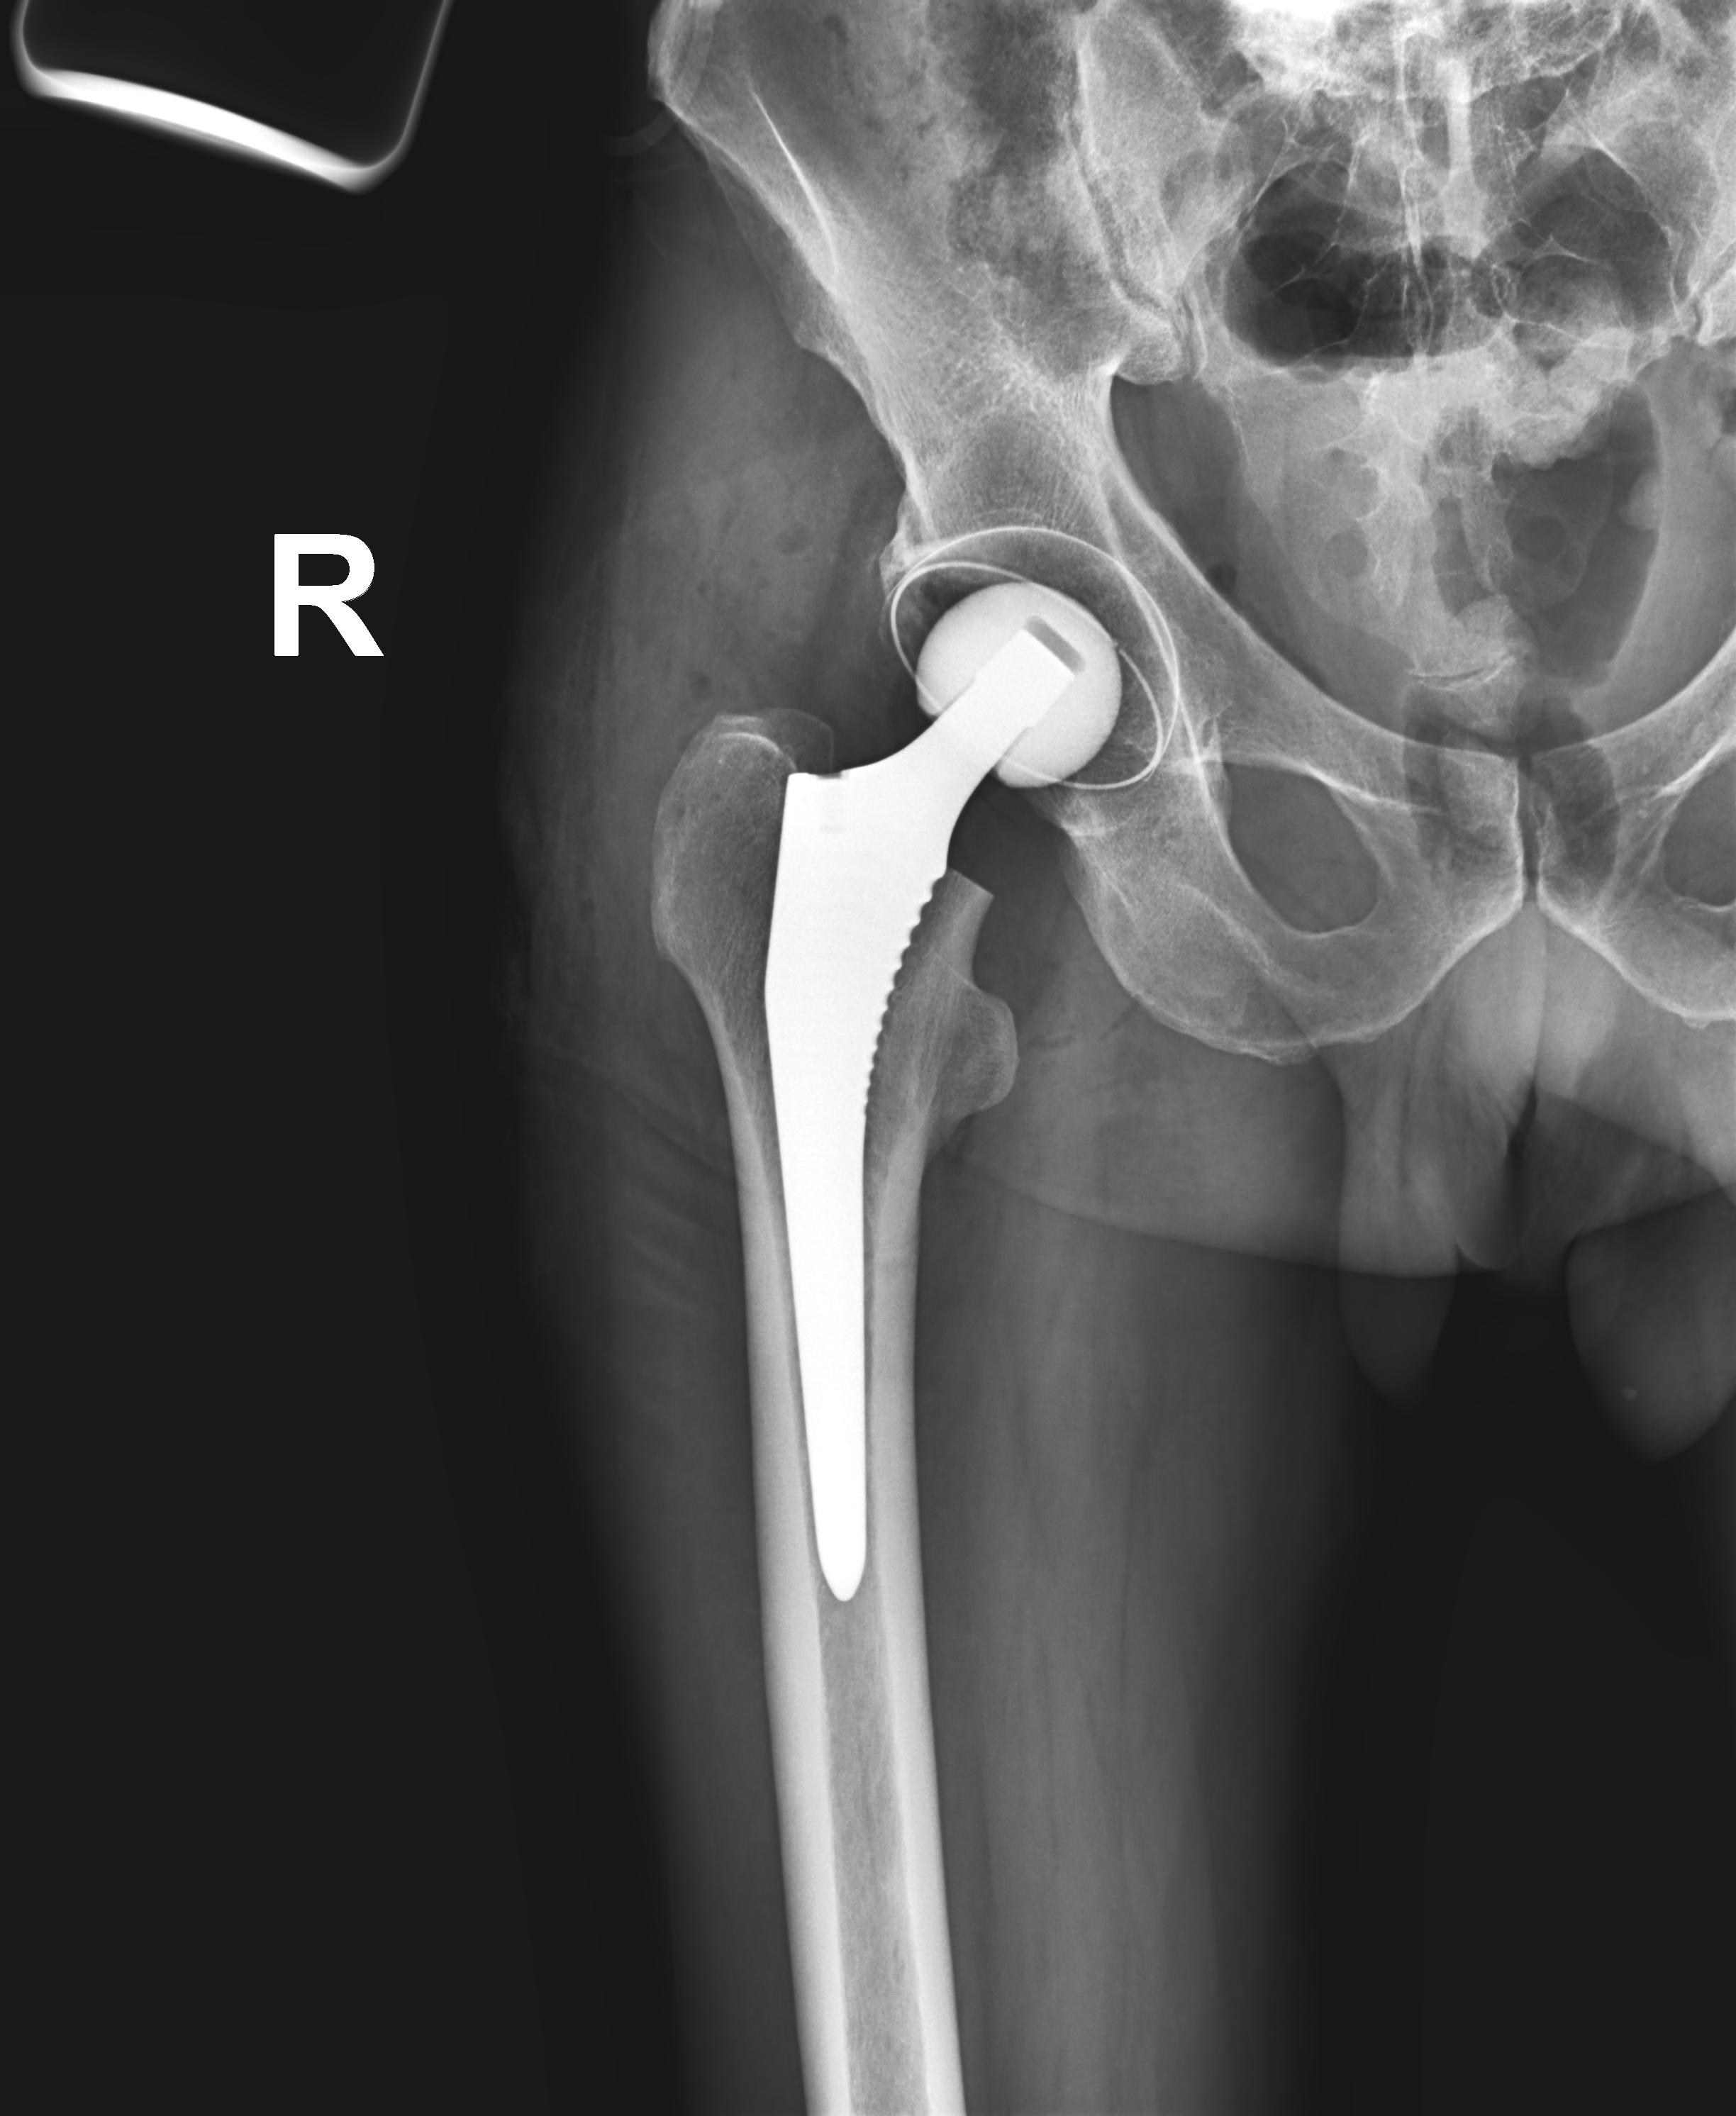

Целью эндопротезирования тазобедренного сустава является уменьшение болевого синдрома и восстановление функции сустава. Замена сустава – эффективный, а порой и единственный способ восстановления функции сустава, позволяющий значительно улучшить качество жизни человека.

Во время операции пораженные компоненты сустава заменяются на эндопротез, повторяющий анатомическую форму здорового сустава и позволяющий выполнять необходимый объем движений. Для изготовления современных эндопротезов используется керамика, металл и полимеры, которые обладают высокой прочностью и хорошей приживаемостью в организме человека. Поэтому срок их службы составляет в среднем 15-20 лет. При износе эндопротеза его заменяют новым.

Протезы тазобедренного сустава различают по типу фиксации:

- эндопротезы цементной фиксации;

- эндопротезы бесцементной фиксации.

В том случае, если разрушена только хрящевая часть сустава, при сохранности головки бедренной кости, есть возможность установки колпачкового эндопротеза (протезирование суставной поверхности), что позволяет максимально сохранить костную ткань и обеспечивает максимальную амплитуду движения.